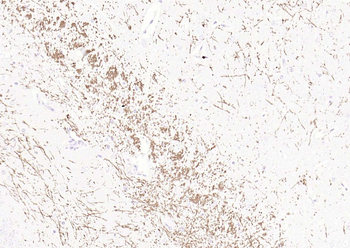

1 ml, 100 μl, 500 μl, 200 μl - MBP Rabbit Polyclonal Antibody [orb11027]Featured

IF, IHC-Fr, IHC-P, WB

Human, Mouse, Rat

Bovine, Canine, Equine, Porcine, Rabbit, Sheep

Rabbit

Polyclonal

Unconjugated

50 μl, 100 μl, 200 μl - Notch1 Rabbit Polyclonal Antibody [orb500788]Featured